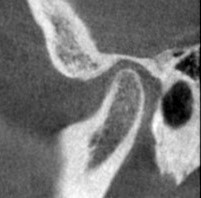

右側の関節のCTスキャンです。

こちらも同じくです。

両側音が鳴るのもうなずけます。

この状態になった時のこの患者さんのCTスキャンの比較はこちらです。

治療前 右側

治療後 右側

関節圧迫が取れているのがわかるでしょうか?

これが治療後の状態です。

赤い線は耳の穴です。

顎関節は耳の穴の裏側に位置します。

耳の穴を関節が圧迫していたらどうなりますか?